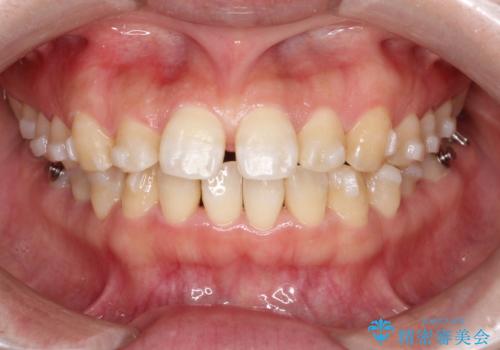

【インビザライン】前歯のすきまを閉じたい

- 前歯の隙間を主訴に来院されました。

インビザライン にて治療を行い、歯並びを改善することができました。